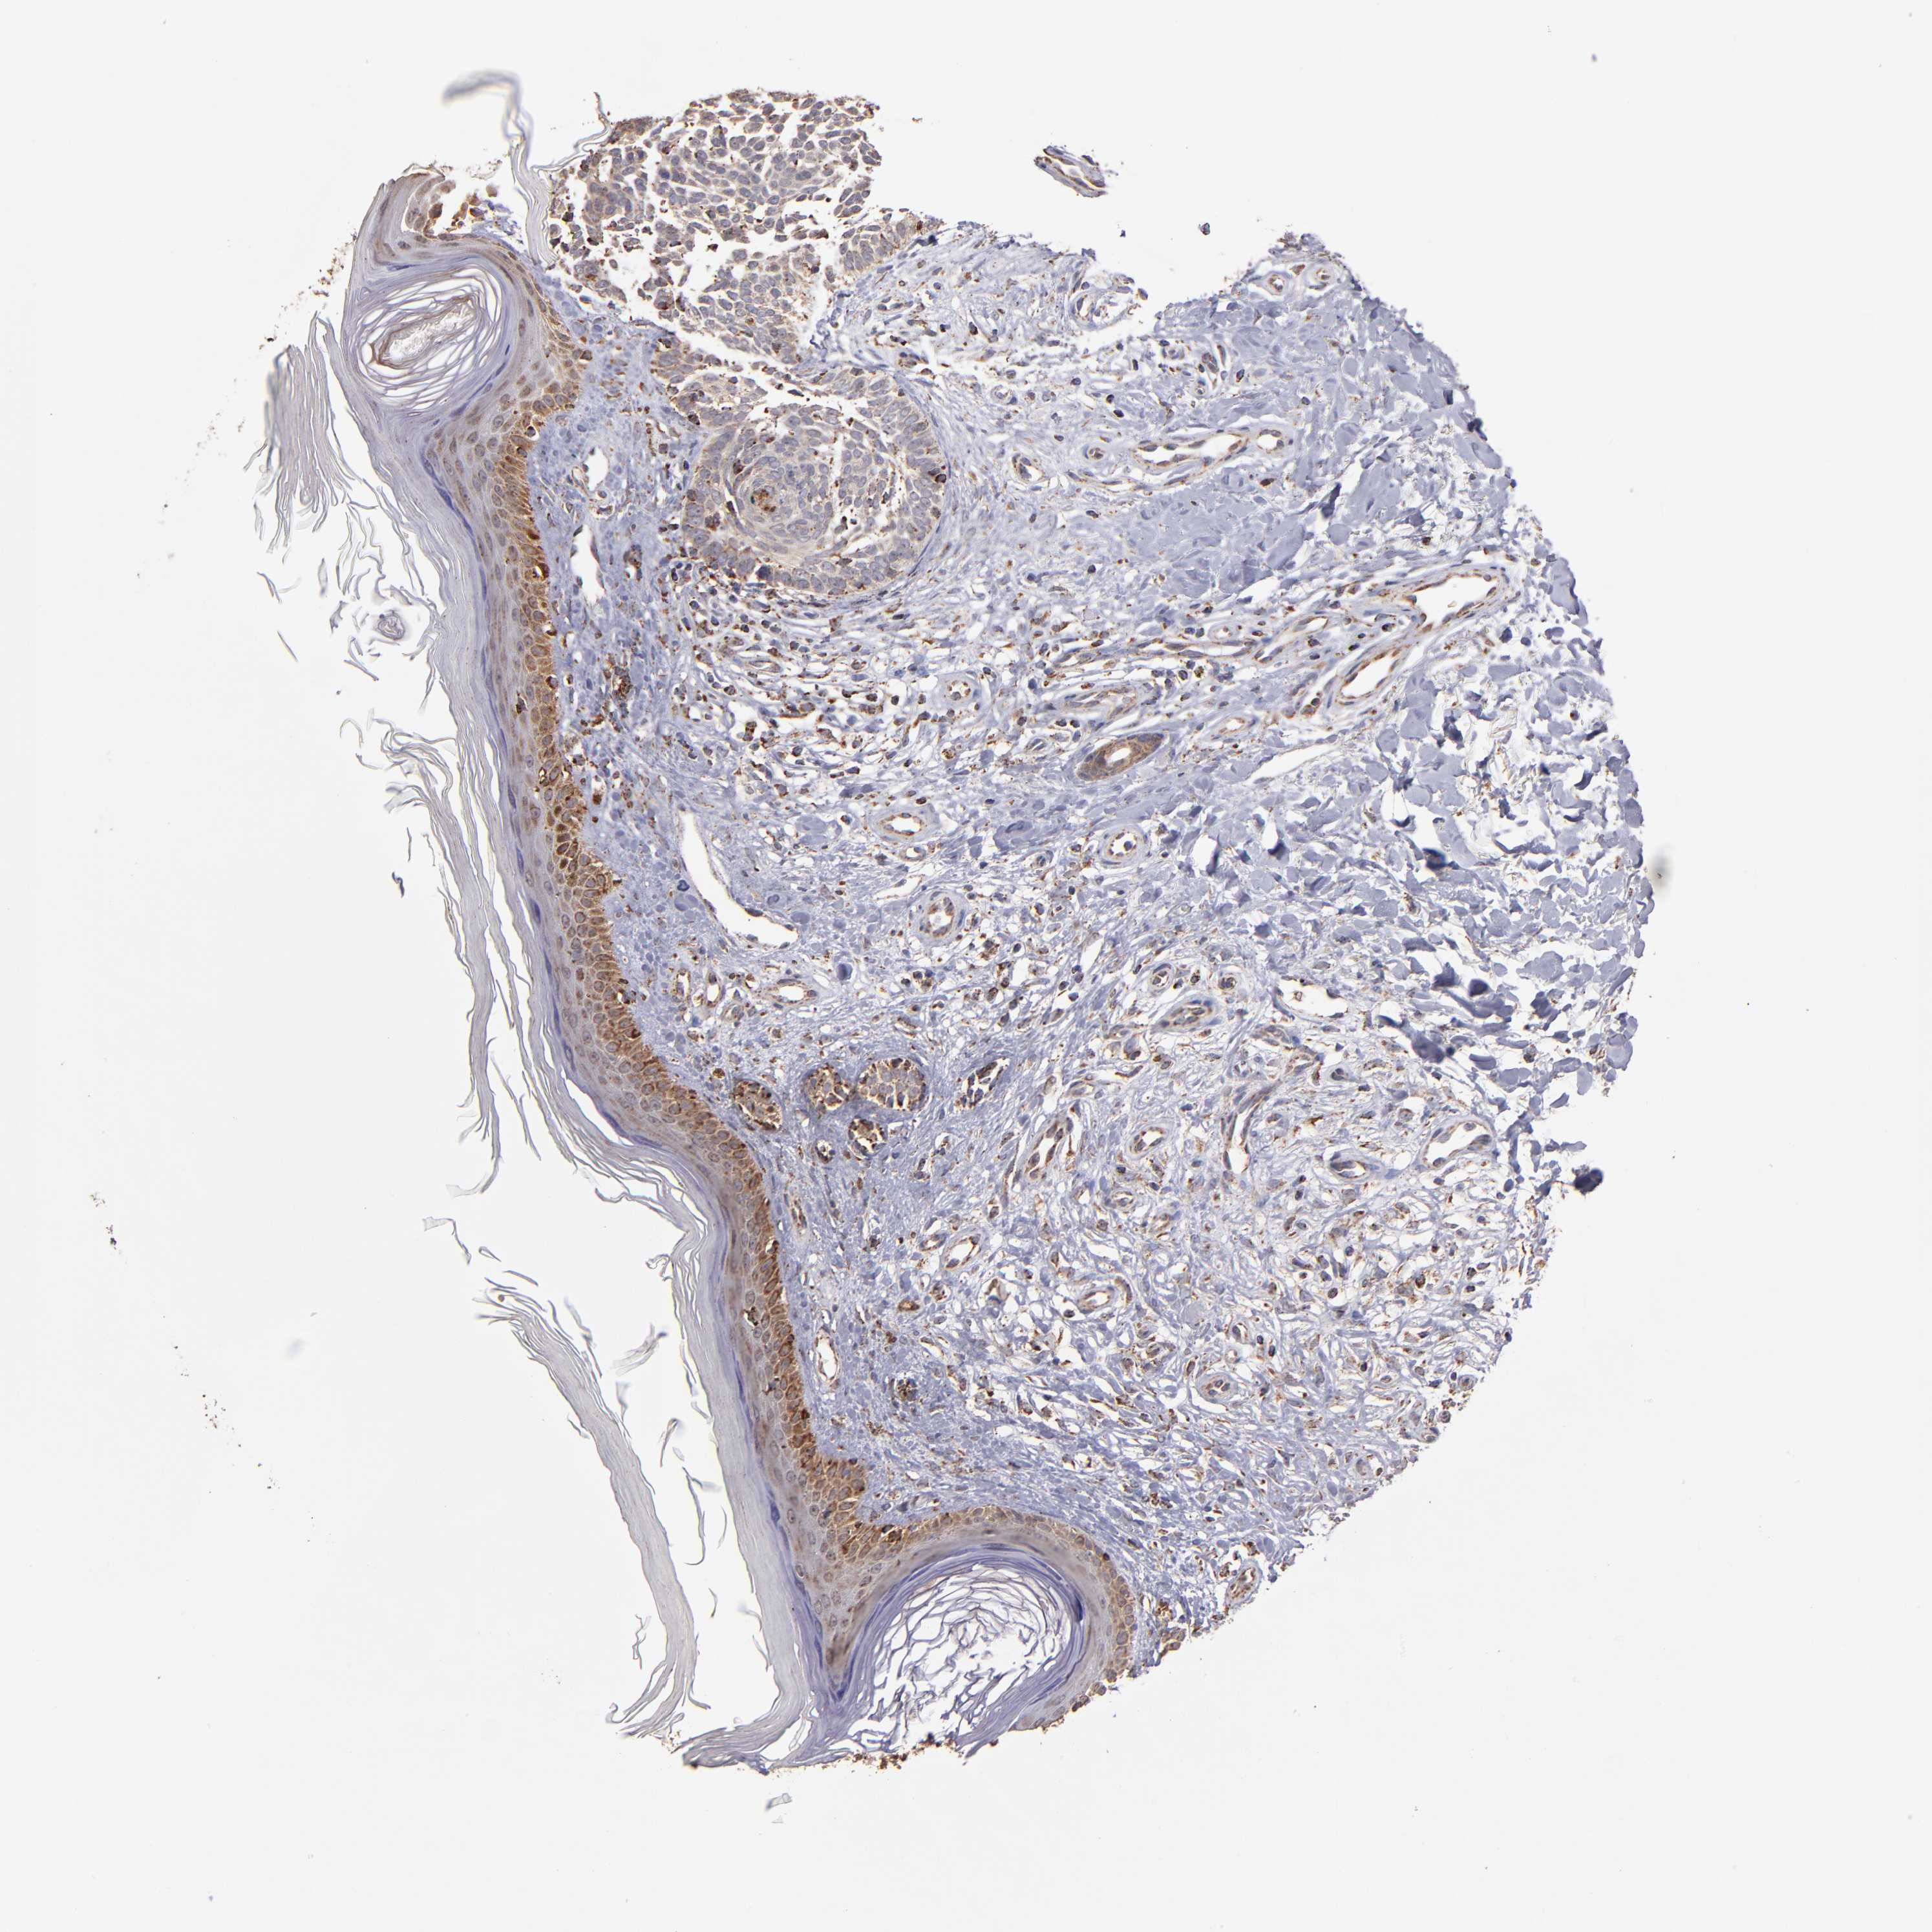

SKIN CANCER - Protein expressioni

A mouse-over function shows sample information and annotation data. Click on an image to view it in a full screen mode. Samples can be filtered based on level of antibody staining by selecting one or several of the following categories: high, medium, low and not detected. The assay and annotation is described here.

Antibody stainingi

Antibody staining in the annotated cell types in the current human tissue is reported as not detected, low, medium, or high, based on conventional immunohistochemistry profiling in selected tissues. This score is based on the combination of the staining intensity and fraction of stained cells.

Each image is clickable and will lead to virtual microscopy that enables deeper exploration of all samples and also displays staining intensity scores, fraction scores and subcellular localization as well as patient and tissue information for each sample.

Antibody HPA003010

Staining

High

Medium

Low

Not detected

Intensity

Strong

Moderate

Weak

Negative

Quantity

>75%

75%-25%

<25%

None

Location

Nuclear

Cytoplasmic/membranous

Cytoplasmic/membranous,nuclear

Squamous cell carcinoma, NOS

Basal cell carcinoma